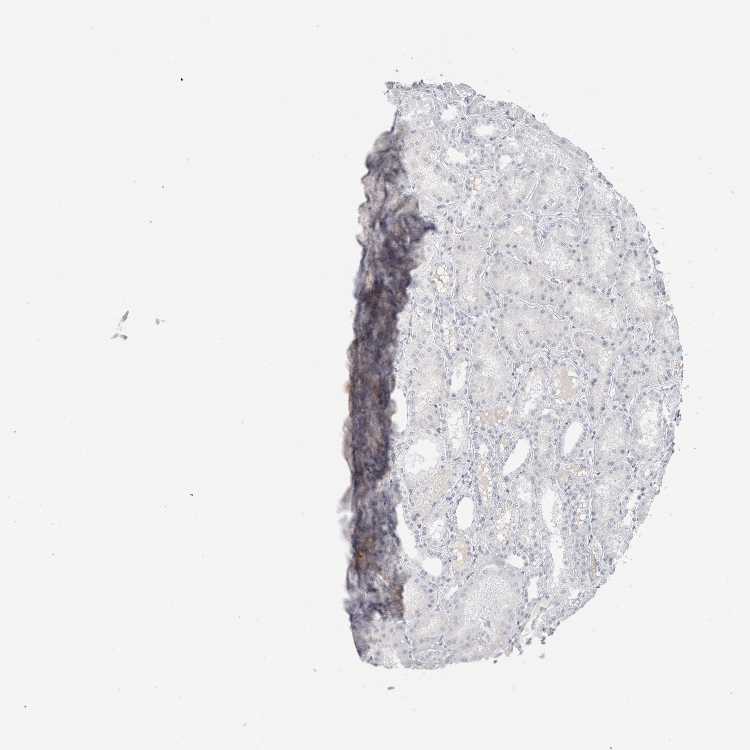

KIDNEY - Antibody stainingi

Antibody staining in the annotated cell types in the current human tissue is reported as not detected, low, medium, or high, based on conventional immunohistochemistry profiling in selected tissues. This score is based on the combination of the staining intensity and fraction of stained cells.

Each image is clickable and will lead to virtual microscopy that enables deeper exploration of all samples and also displays staining intensity scores, fraction scores and subcellular localization as well as patient and tissue information for each sample.

Antibody HPA044337Antibody CAB026009

Bowman's capsule Not detected-

Cells in glomeruli Not detectedNot detected

Cells in tubules -Not detected

Collecting ducts Medium-

Distal tubules Medium-

Proximal tubules (cell body) Not detected-

Proximal tubules (microvilli) High-